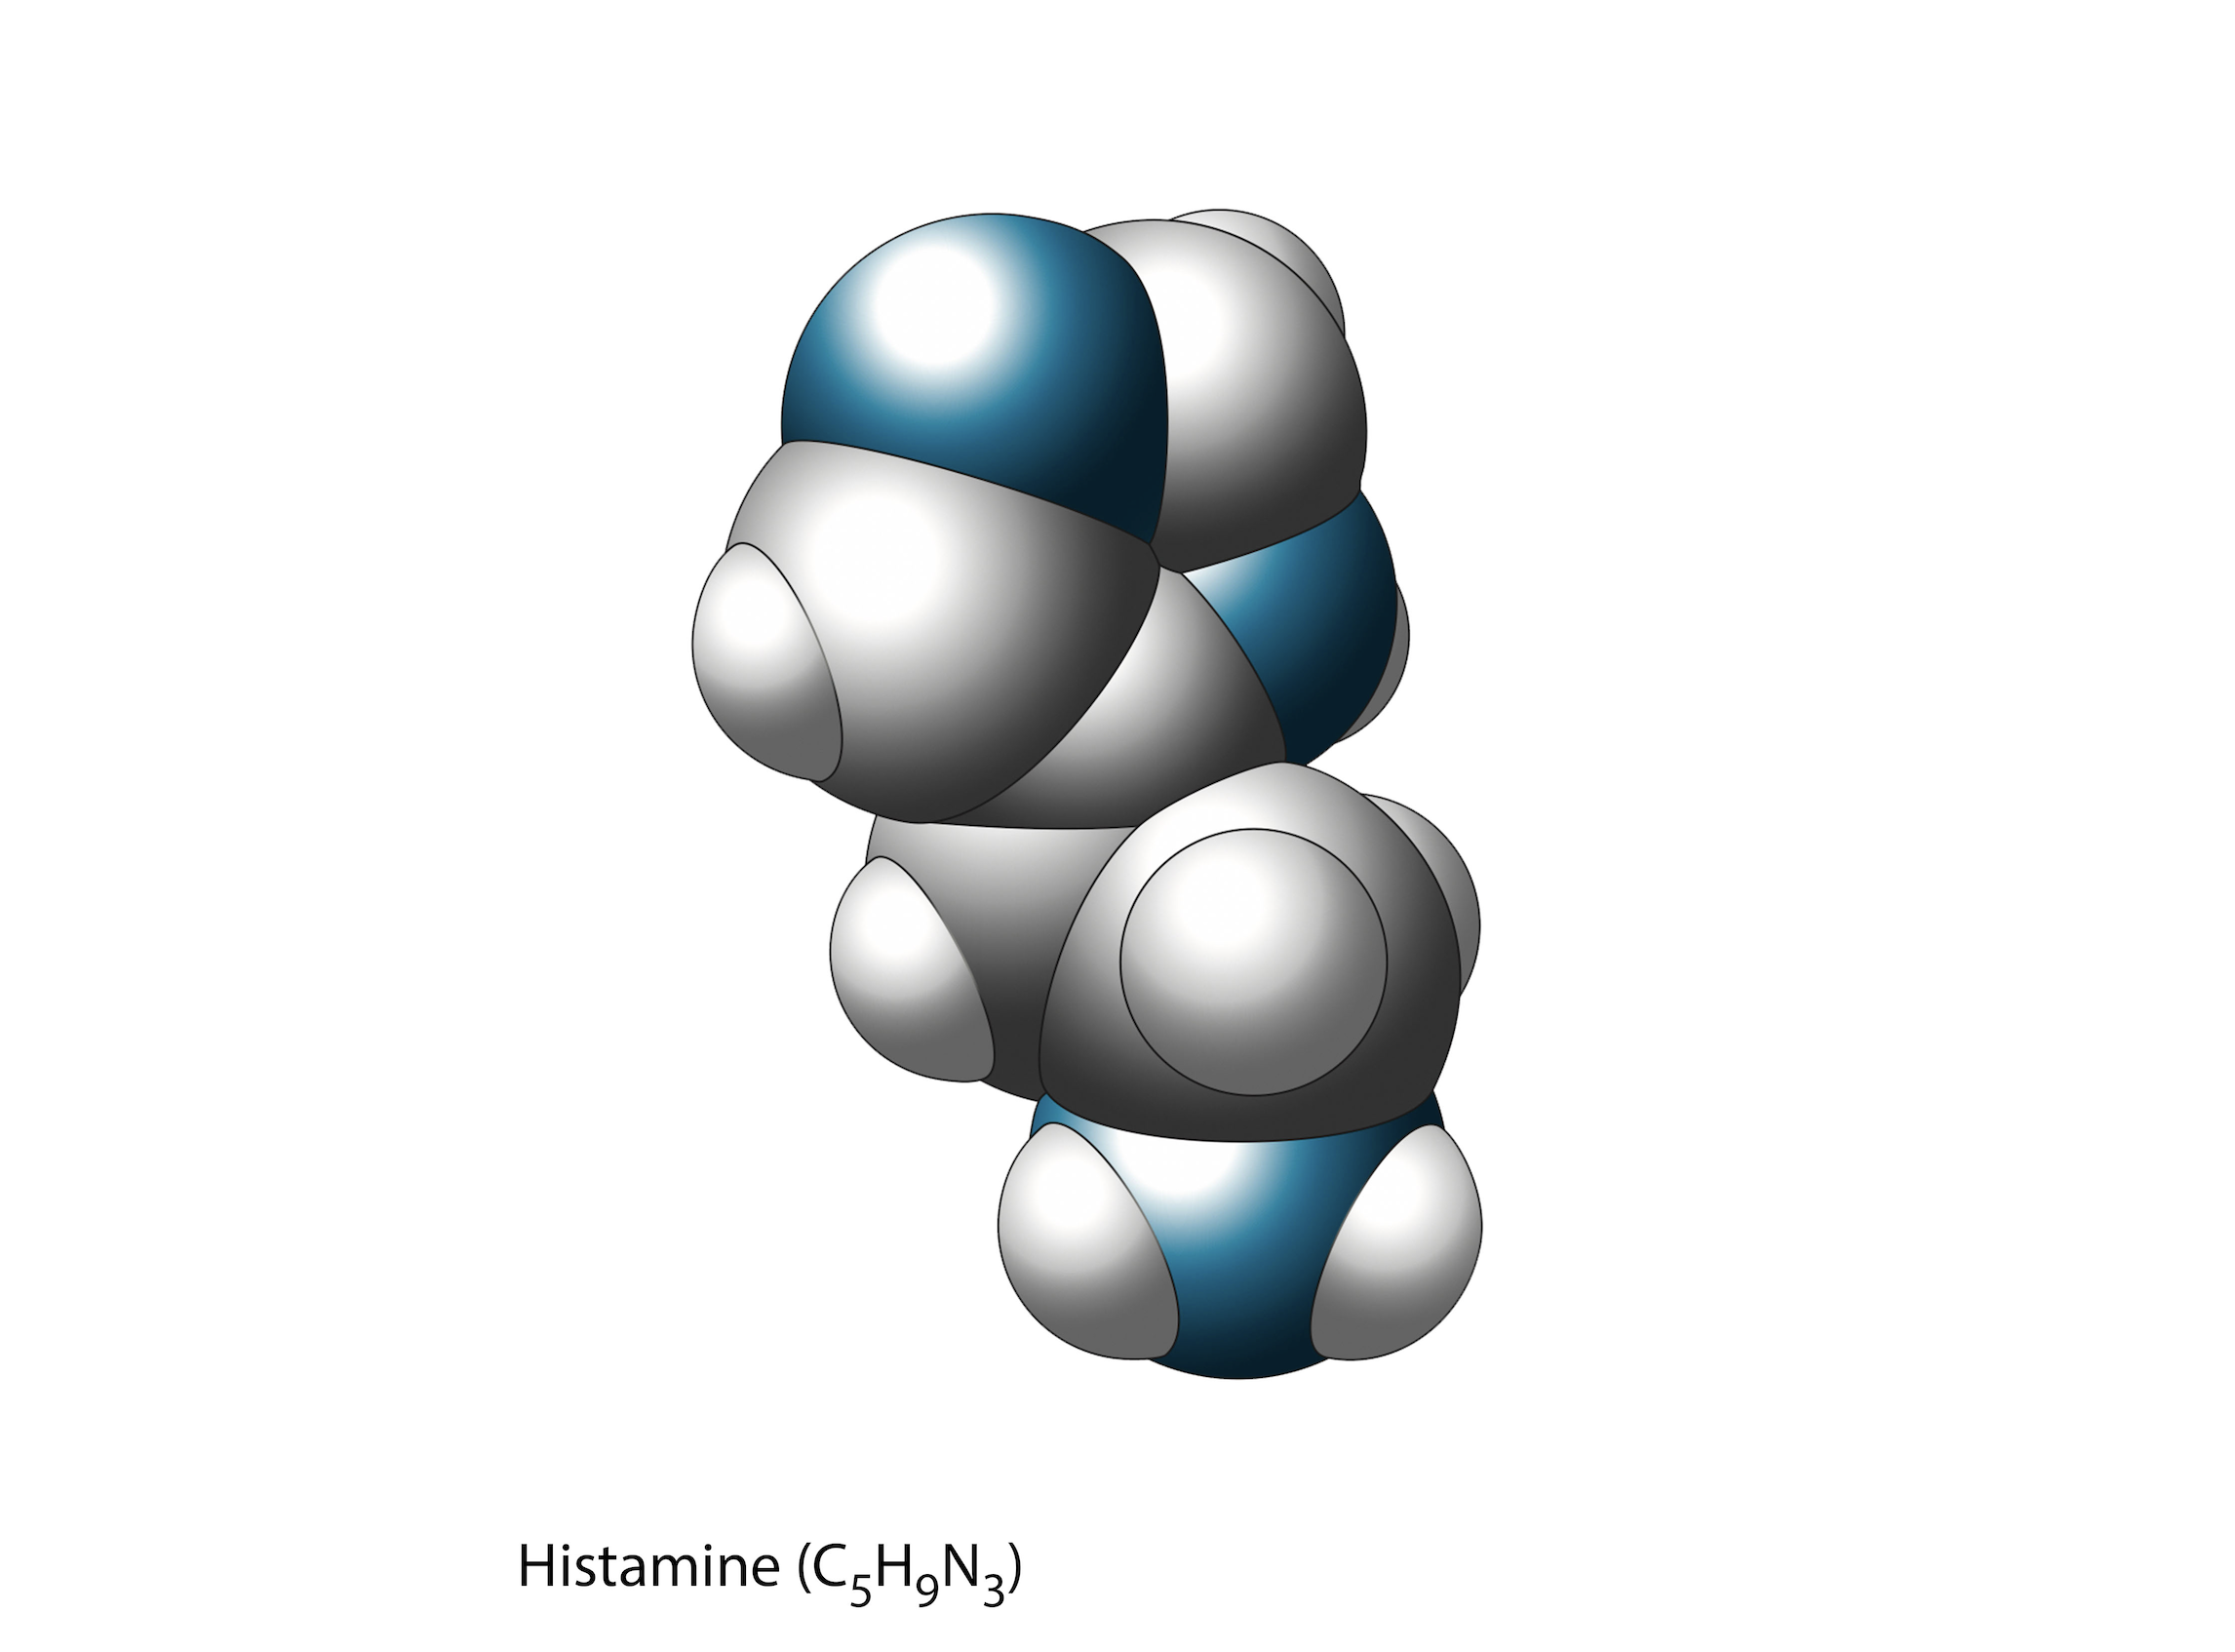

Biomedical art is a form of biological illustration that helps record and disseminate medical, anatomical, and related knowledge. It translates complex technical medical information into visual artwork to support research, patient care and education, public relations, and marketing objectives.